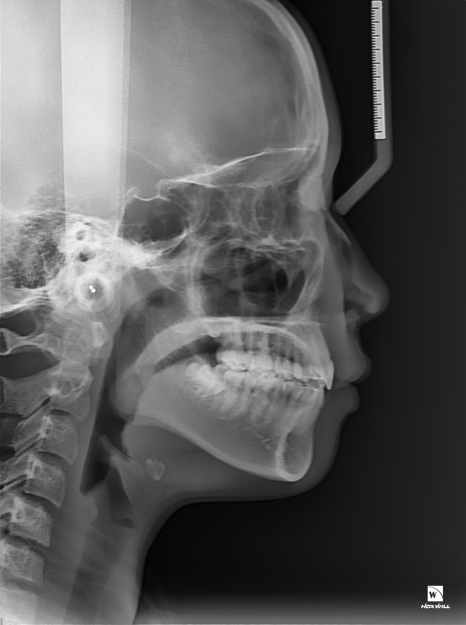

교정 종결 후 돌출 입이 해결된 모습

상, 하악의 부정교합이 개선된 덕분에

심미적으로도 보기가 좋지 않았던

사례자분의 콤플렉스 또한 해결되어

측면에서 보았을 때 더욱 심했던

돌출입이 확연히 개선되었답니다.

진료 종결 후 입을 가리지 않고

밝게 웃으시는 사례자분을 보고

굉장히 뿌듯했던 기억이 납니다 ^^